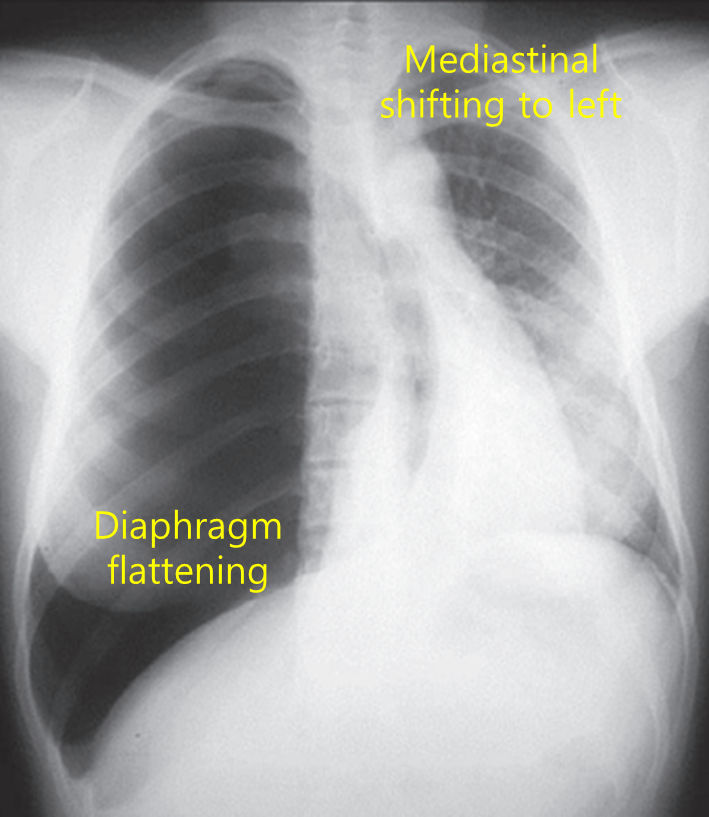

62세 여자가 1시간 전부터 숨을 쉬기가 어렵다고 응급실에 실려왔다. 4년 전부터 만성폐쇄성폐질환으로 흡입제를 매일 사용 중이다. 혈압 80/50 mmHg, 맥박 110회/분, 호흡 29회/분, 체온 36.0°C이다. 오른쪽 가슴에서 호흡음은 들리지 않는다. 가슴 X선 사진이다. 우선 시행할 처치는?

Img | CXR: 우측 폐 bronchovascular marking 사라짐, 심장 및 기도 좌측 이동 |

Imp: 긴장성 기흉(tension pneumothorax)

V/S이 unstable하고 mediastinal shift가 관찰되므로 긴장성 기흉 진단 하, 굵은 바늘 삽입을 시행한다.

• CXR에서 우측 폐의 폐혈관 음영이 완전히 사라졌고, 심장과 기도가 좌측으로 이동한 소견으로 보아 긴장성 기흉이 의심된다.

긴장성 기흉 | • V/S unstable • CXR: Mediastinal shift • 즉각적인 바늘 감압 → 이후 흉관 삽입 |